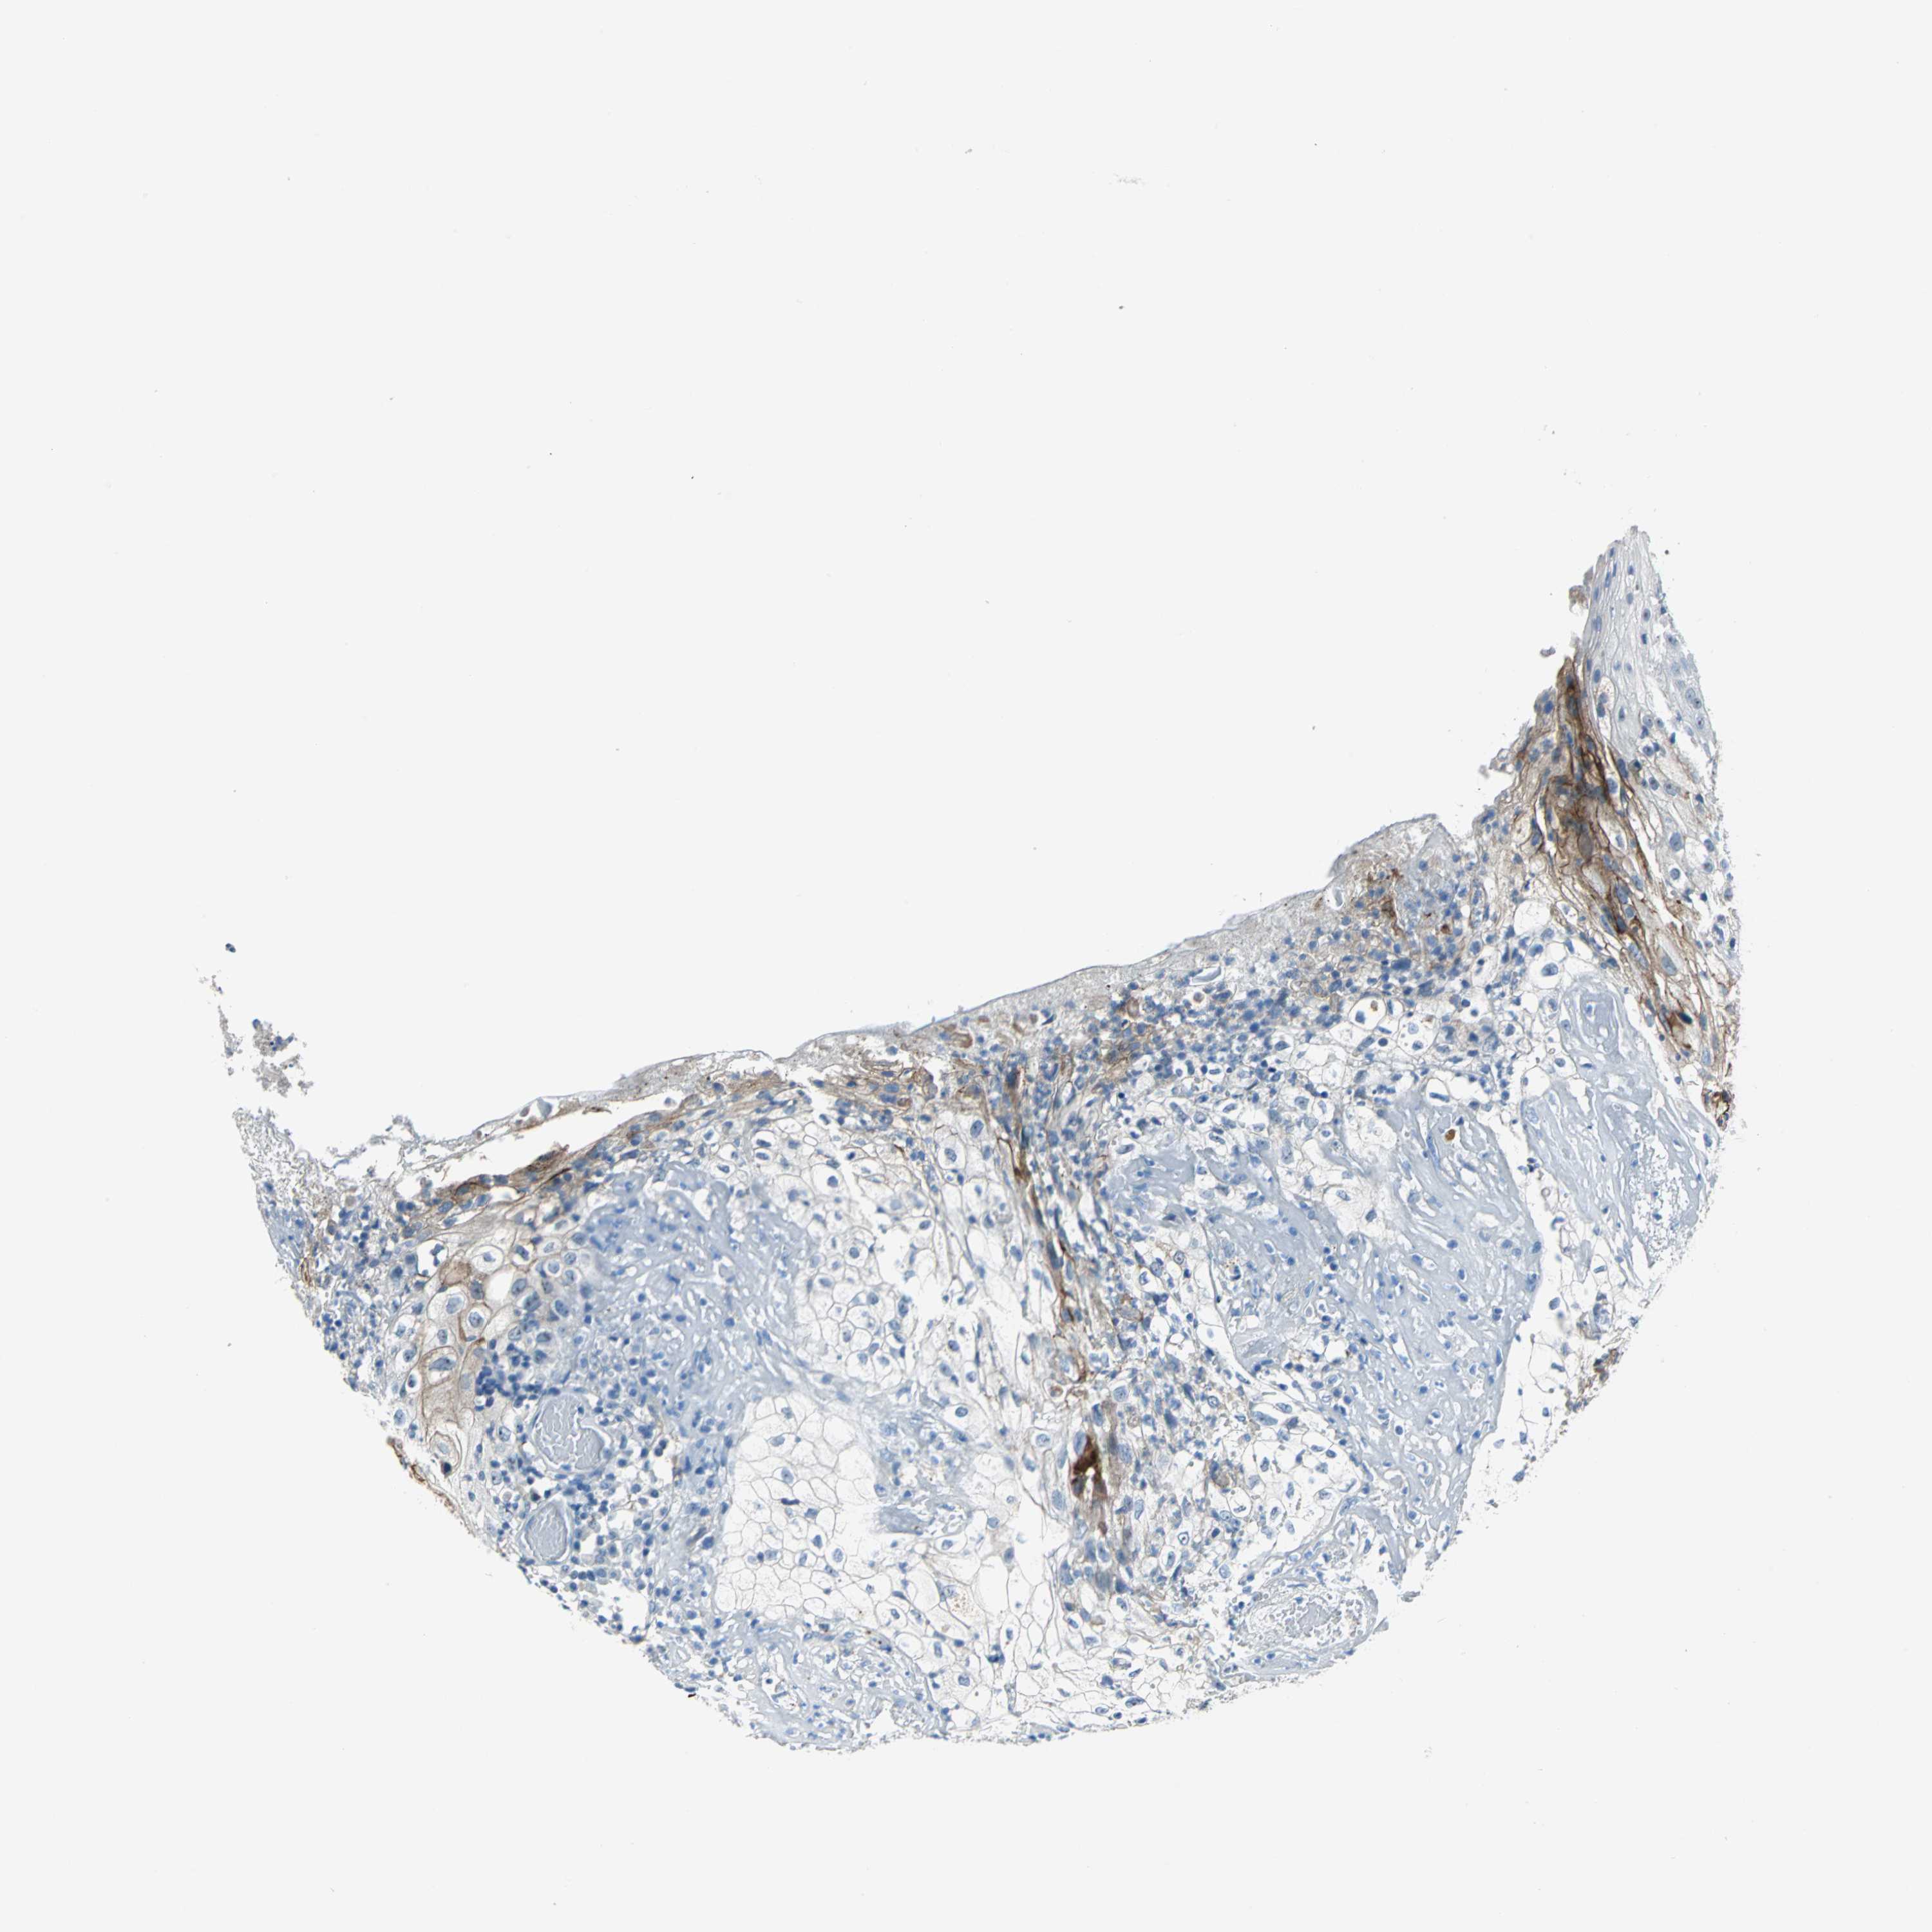

SKIN CANCER - Protein expressioni

A mouse-over function shows sample information and annotation data. Click on an image to view it in a full screen mode. Samples can be filtered based on level of antibody staining by selecting one or several of the following categories: high, medium, low and not detected. The assay and annotation is described here.

Antibody stainingi

Antibody staining in the annotated cell types in the current human tissue is reported as not detected, low, medium, or high, based on conventional immunohistochemistry profiling in selected tissues. This score is based on the combination of the staining intensity and fraction of stained cells.

Each image is clickable and will lead to virtual microscopy that enables deeper exploration of all samples and also displays staining intensity scores, fraction scores and subcellular localization as well as patient and tissue information for each sample.

Antibody HPA005895

Antibody CAB013536

Squamous cell carcinoma, NOS

Basal cell carcinoma